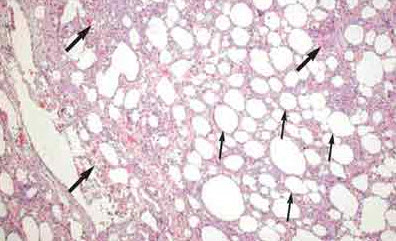

A left lower lobectomy is performed. Exogenous sections from the left lower lobe specimen show an increased number of macrophages and lipid-laden macrophages ("lipophages"). Some histiocytes show fine vacuoles; others form multinucleated foreign-body giant cells. Chronic lymphoplasmacytic inflammation and a variable amount of fibrosis are apparent in other areas. There is no evidence of malignancy (Figure 3). These findings, along with the patient's use of mineral oil, confirm the diagnosis of lipoid pneumonia.

Lipoid pneumonia is referred to as the "golden pneumonia" because of its histologic appearance. The color results from the filling of alveoli with foamy macrophages that are packed with small lipid droplets and cellular debris.